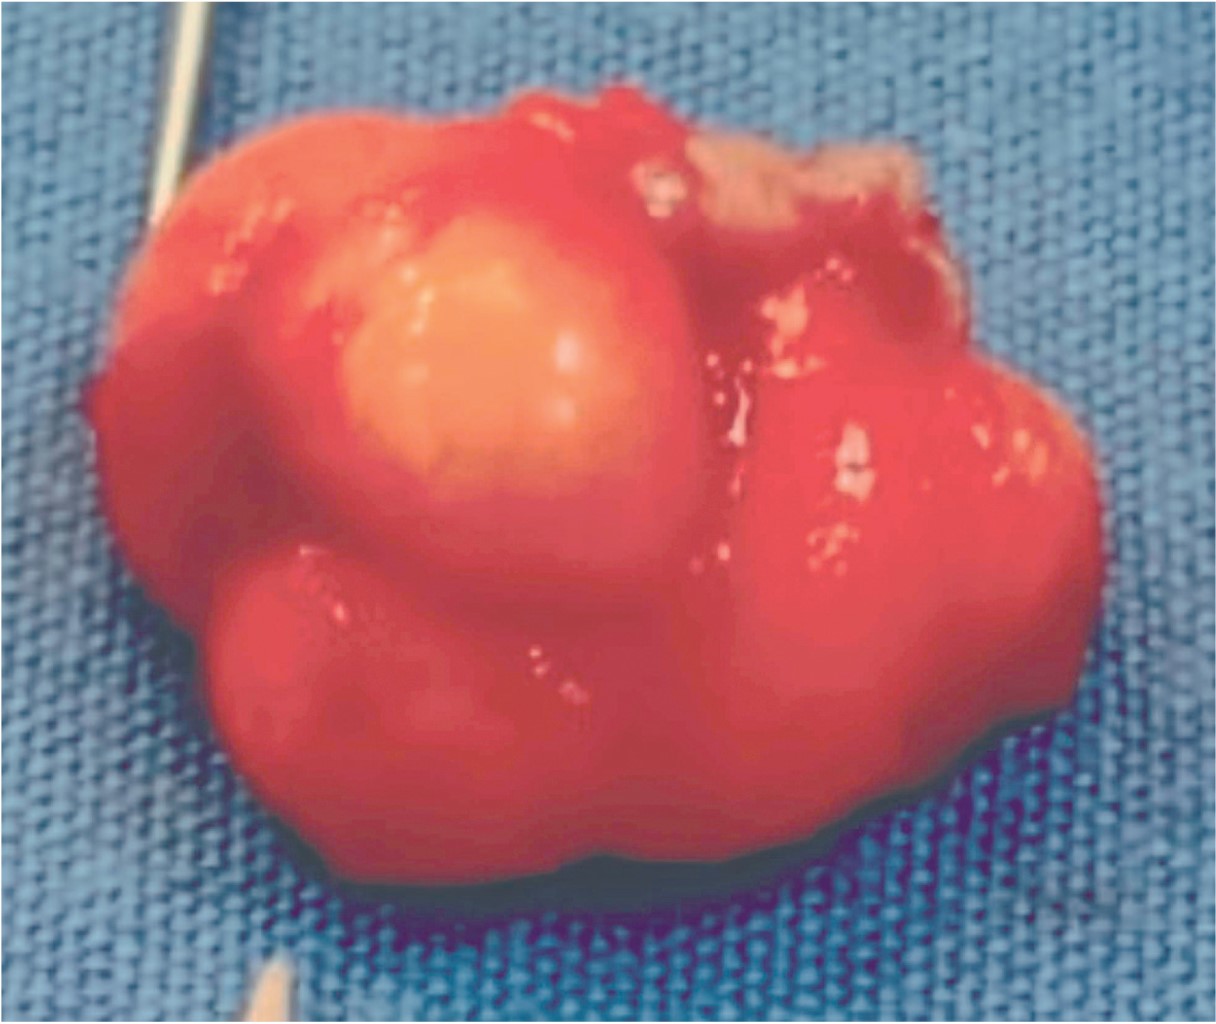

Con el diagnóstico presuntivo de lipoma en mucosa labial inferior, el paciente es referido al Servicio de Cirugía Dermatológica, en donde se realiza extirpación de la lesión con cierre directo (Figuras 2 y 3). El estudio histopatológico describe al corte la presencia de una neoformación bien circunscrita, constituida por numerosos adipocitos maduros de características normales, con algunos vasos dilatados y congestionados (Figuras 4, 5 y 6) confirmando con estos hallazgos el diagnóstico de lipoma. En el seguimiento postoperatorio del paciente únicamente se presenta cicatriz eutrófica; dos meses posteriores a la cirugía se da de alta.

Figura 2

Figura 3